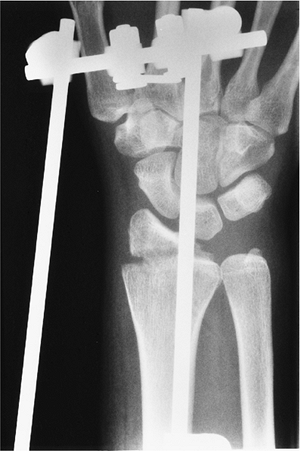

![]() |

FIGURE 9-8 PA radiograph of a Chauffeur’s fracture during reduction with an external fixation.

|